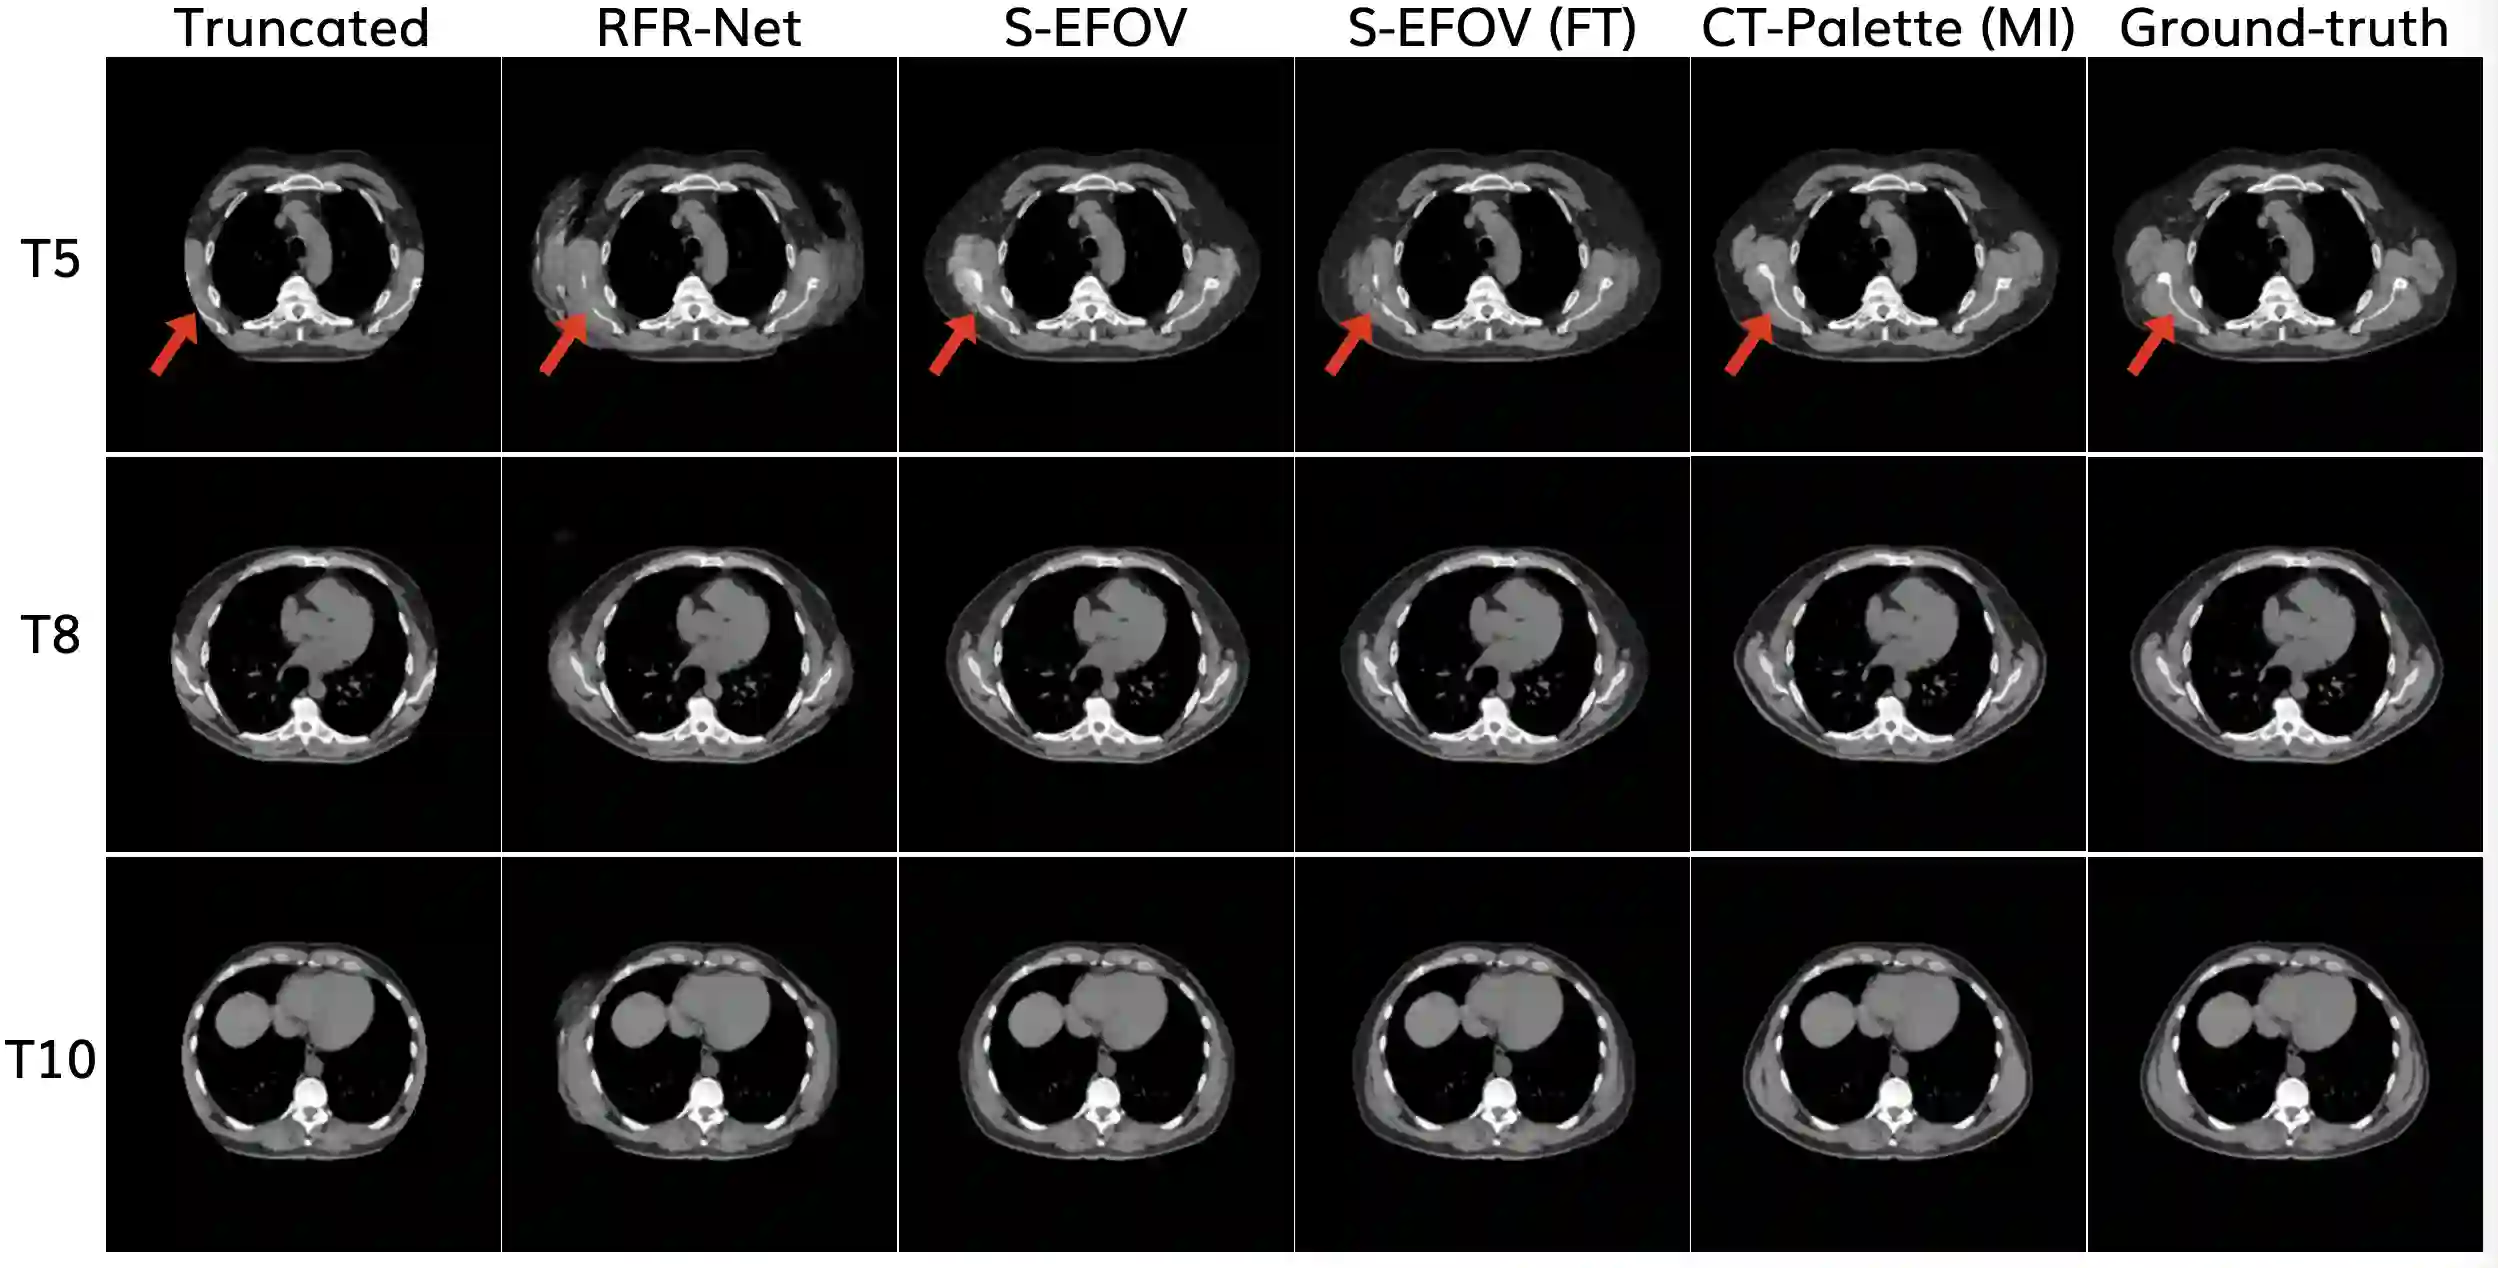

Field-of-view (FOV) recovery of truncated chest CT scans is crucial for accurate body composition analysis, which involves quantifying skeletal muscle and subcutaneous adipose tissue (SAT) on CT slices. This, in turn, enables disease prognostication. Here, we present a method for recovering truncated CT slices using generative image outpainting. We train a diffusion model and apply it to truncated CT slices generated by simulating a small FOV. Our model reliably recovers the truncated anatomy and outperforms the previous state-of-the-art despite being trained on 87% less data.